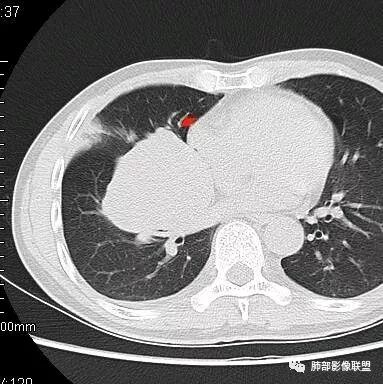

南边:有老师问为啥考虑中叶支气管受压?不是支气管来源的?

1、主体病灶在下叶

2、支气管腔还在,有移位

换个角度考虑一下:如果中叶支气管壁起源的病灶会如何变化?

应该是支气管壁局部改变,病灶固定在中叶支气管周围,推移其它结构

换句话说,如同大树生长,是不是以根为基础,朝周围长,不应该是长大一点让自己的树根部分推开一点

就算是扭扭曲曲生长,根基一般不动

这一个类圆形,边界光滑,明显膨胀生长为主,如果起源中叶支气管,按理中叶支气管不动,固定在中叶支气管上,推移其他结构

但是现在的片显示,其主体在下叶,中叶支气管壁由下朝上有推移

南边:就不符合这个原理

初学者:如果中叶病灶,叶间裂应该下推,也不会上推

而且支气管內密度较高是粘液栓,远端支气管也是通畅,所以支气管内是因为受压所以痰液引流不畅。